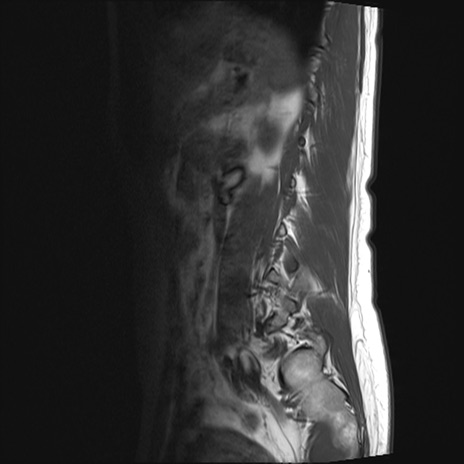

腰椎MRI

STIR(矢状断像)